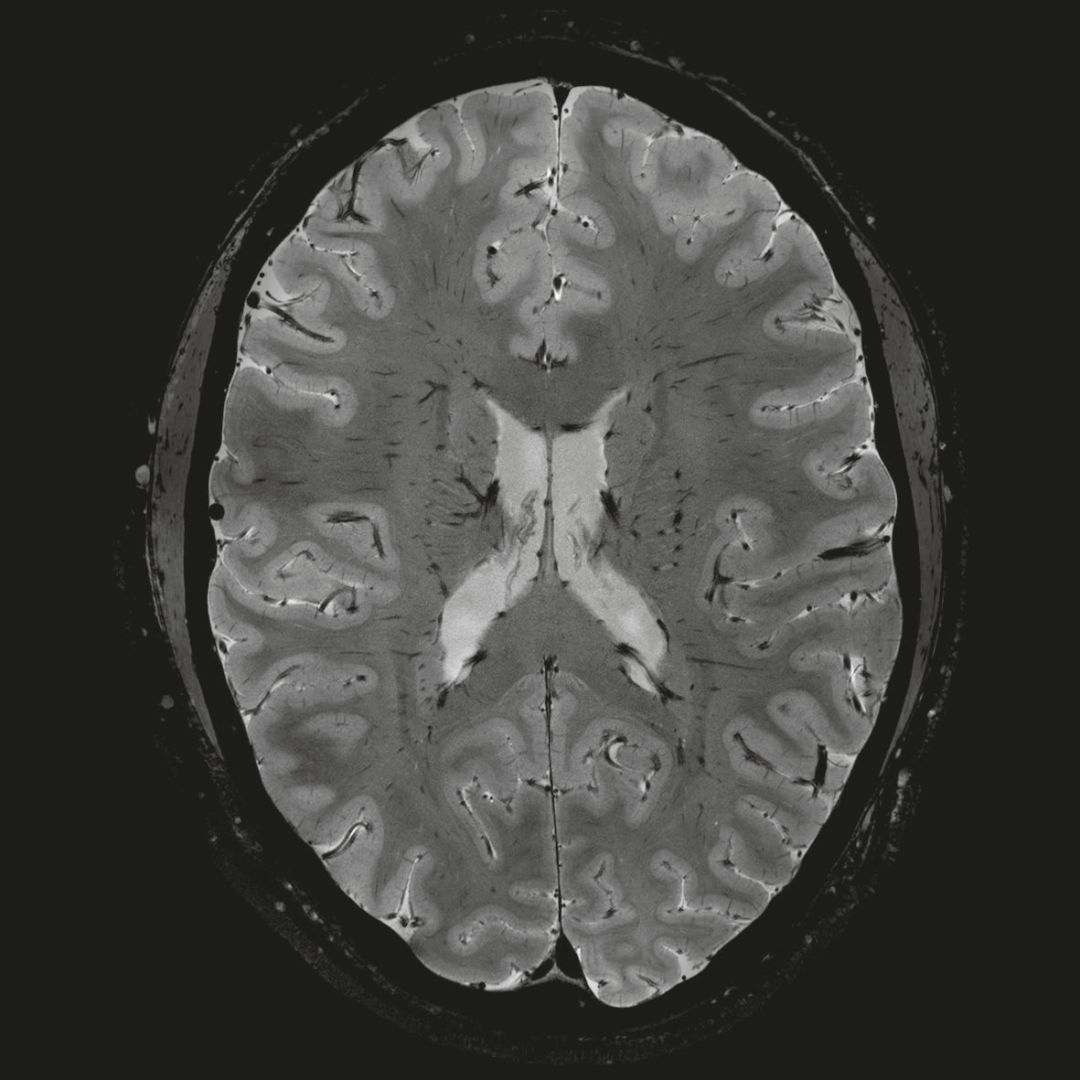

0.8毫米的各向同性分辨率:精確劃分灰質(zhì)和白質(zhì)

超精細(xì)的解剖細(xì)節(jié):T2對(duì)比

0.17 x 0.17 x 0.8毫米分辨率超高。